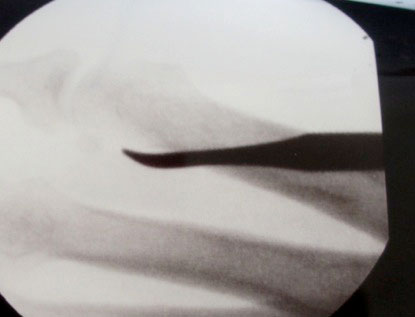

Proximale Schaftosteotomie:

Es handelt sich hier um eine medial schließende Osteotomie des proximalen Metatarsale­schaftes bei Typ 2 oder Typ 3 Fehlstellungen. Die Osteotomie wird am Apex der Fehlstellung unter BV Kontrolle durchgeführt (Abb. 21). Am medialen Rand des Metatarsale 5 Schaftes erfolgt eine Stichinzision (Abb. 22). Von hier aus werden mit dem Raspatorium die Weichteile vom Knochen abgeschoben. Anschließend wird die kurze 2 mm Shannon Fräse senkrecht eingeführt und ein Bohrloches leicht lateral der Schaftmitte gesetzt (Abb. 23). Ausgehend vom Bohrloch wird der Metatarsale-5-Schaft subtotal nach medial durchtrennt. Die laterale Kortikalis sollt hierbei erhalten bleiben. Wird die Fräse leicht von dorsolateral eingebracht, wird des Metatarsale 5 Köpfchen beim Schließen der Osteotomie etwas angehoben, was meist gewünscht wird (Abb. 24). Der Drehpunkt der Fräse ist die Hautinzision. Um Haut­läsionen zu vermeiden darf (wie bei allen anderen minimalinvasiven Verfahren auch) auf keinen Fall gehebelt werden. Nach Durchtrennung der medialen Kortikalis wird die Osteo­tomie durch manuellen Druck geschlossen. Die Osteotomieebene kann direkt nach medial gelegt werden oder wie hier im Bild leicht schräg nach distal-medial. Der Vorteil der Schräg­osteotomie besteht in einer größeren Osteotomiefläche und damit der höheren Stabilität (Abb. 25). Es folgt das obligate Ausdrücken des Knochenmehls und das ausgiebige Aus­spülen der Wunde. In der Wunde verbleibendes Knochenmehl führt neben ungewollten Ossifikationen zu lange anhaltenden Weichteilreaktionen die klinisch von Wundinfektionen oft schwer zu unterscheiden sind. Der Verschluss der Wunde erfolgt durch eine Einzelknopf­naht.